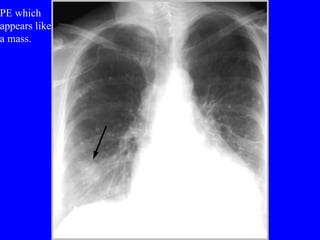

Diagnosis CXR Usually reveals a non specific abnormality.  14% normal Classic abnormalities include: Westermark’s Sign - focal oligemia Hampton’s Hump - wedge shaped density Enlarged Right Descending Pulmonary Artery (Palla’s sign)

Diagnosis CXR Usuallyreveals a non specific abnormality. 14% normal Classic abnormalities include: Westermark’s Sign - focal oligemia Hampton’s Hump - wedge shaped density Enlarged Right Descending Pulmonary Artery (Palla’s sign)

PE which appears like a mass.